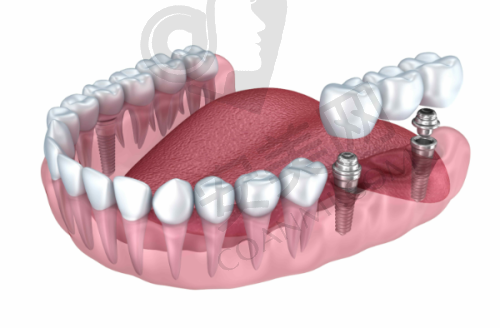

韩国登腾种植牙是国内外有名的种植牙品牌。它采用了精良的表面处理技术,能够促进种植体与牙槽骨的快速结合,大大缩短了种植体的愈合时间。登腾种植牙的稳定性非常好,能够承受较大的咀嚼压力,确保患者在日常生活中正常使用。而且,它的生物相容性高,能够减少人体对种植体的排异反应,降低感染等并发症的发生几率。此外,登腾种植牙的外观与天然牙齿非常相似,能够达到自然美观的成效,让患者在拥有健康牙齿的同时,也能拥有自信的笑容。

首先,患者需要到乌鲁木齐美奥口腔进行全方面的口腔检查,包括口腔CT扫描等,以确定患者的口腔状况和种植方案。然后,王旭医生会与患者进行详细的沟通,解释种植方案的具体内容和注意事项,患者可以根据自己的情况进行选择和调整。接下来就是种植手术阶段,在局部麻醉下,王旭医生会将韩国登腾种植体植入患者的牙槽骨内。手术后,患者需要按照医生的嘱咐进行休息和护理,等待种植体与牙槽骨愈合。一般需要几个月的时间,待种植体稳定后,再安装全瓷冠。末尾,医生会对患者进行复查,确保种植成效达到预期。